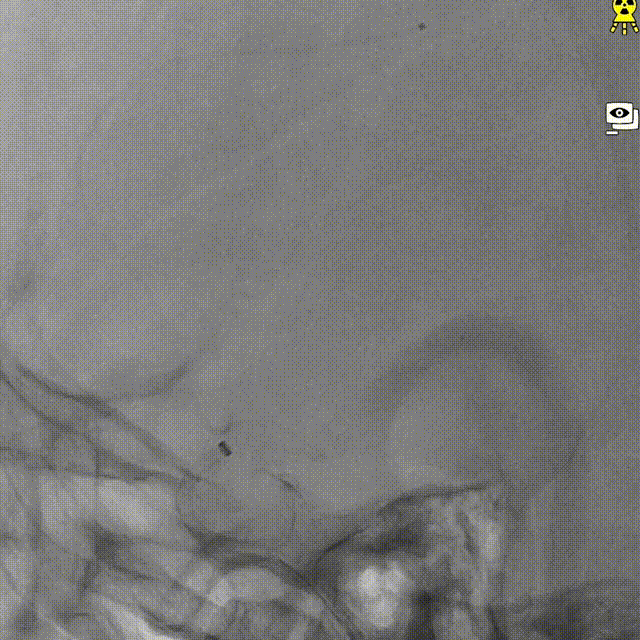

右侧颈内正位造影

右侧颈内侧位造影

载瘤动脉远端血管直径:2.1mm

载瘤动脉近端血管直径:1.8mm

动脉瘤尺寸:瘤颈4.69mm,大小3.25mm*4.21mm*4.24mm;指向右上

近端狭窄:最窄处:0.53mm,远心端2.1mm,近心端2.2mm,长度11.23mm